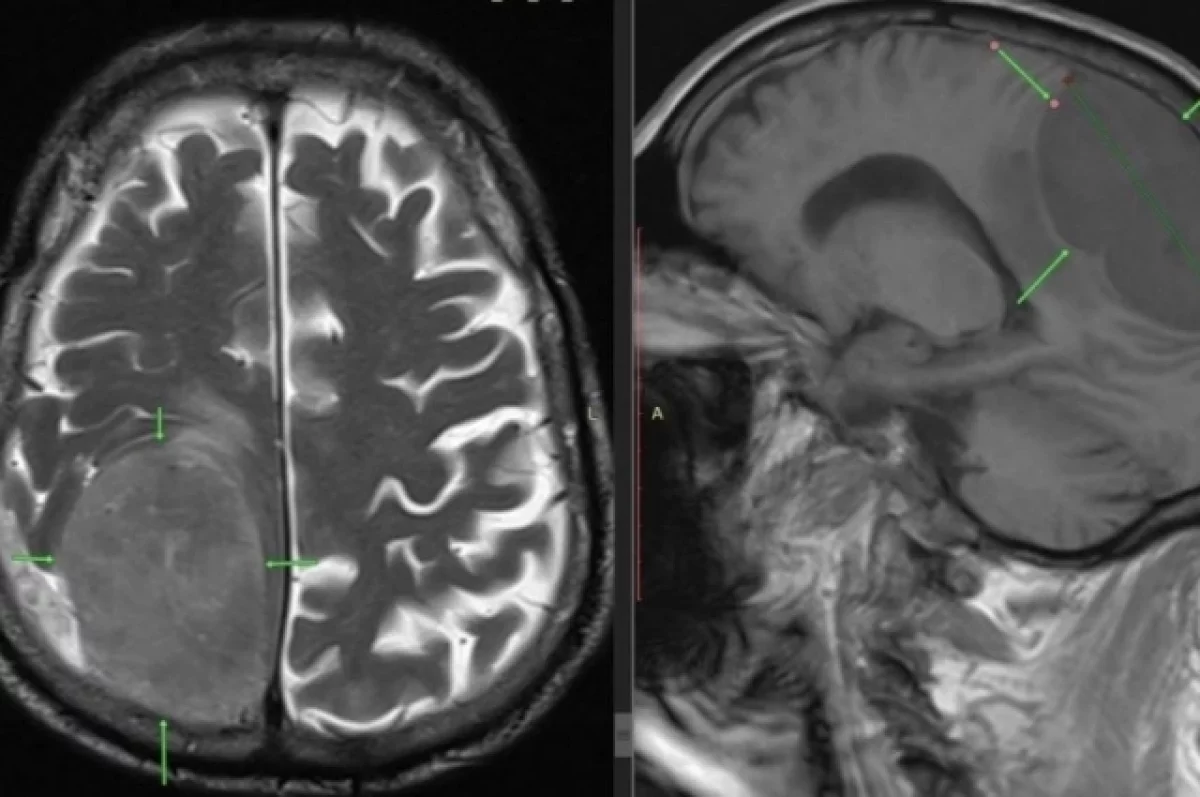

Пациента привезли в больницу с серьезной проблемой: он потерял возможность двигать левой ногой и левой половиной тела. Сначала врачи заподозрили инсульт, но экстренное обследование показало другую причину. Оказалось, что в правой части мозга у пациента росла огромная опухоль размером 8 на 7 сантиметров, которую медики сравнили с лимоном. Именно это новообразование давило на центры, отвечающие за движения левой стороны тела.

К счастью, все прошло успешно. На контрольных снимках после операции не было обнаружено никаких признаков кровотечения, мозг пациента восстановил нормальную форму и размеры.